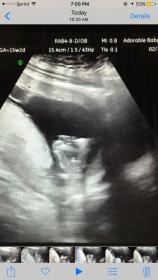

Boy :)

I'd say boy but what gestation is this??x

I'd say boy. What GA is this?

Boy